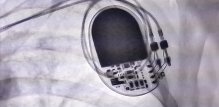

Komplikacije pacemakera Budite prvi i komentirajte! 1 min čitanja Tomislav Stanić mag. educ. philol. croat. Tekst Dana Za vas izdvajamo Piše psihologinja Ljudi koji stalno kasne: Lijenost ili ozbiljan problem? Marija Šimunić 3 min čitanja Članak objavljen: 18-12-2025 Zatvori Podijelite članak Facebook Twitter Whatsapp Viber Kopirajte adresu